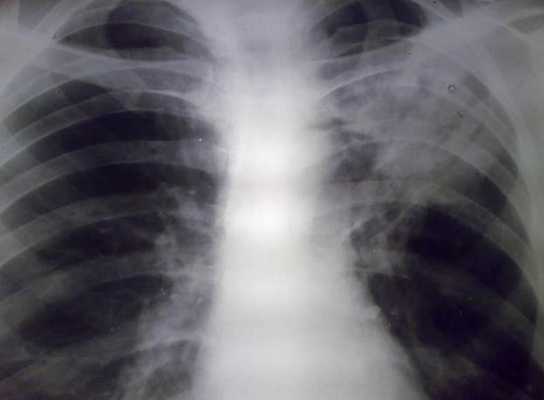

При кардиогенном отеке легких наряду с «матовыми стеклами» наблюдается утолщение междолевой плевры, сетчатая деформация легочного рисунка, а контуры корней легких расширенные и нечеткие.

К дополнительным признакам отека легких на КТ относится увеличение диаметра легочных сосудов, расширение камер сердца и жидкость в плевральной полости.